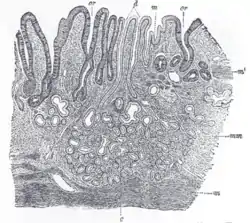

Section of duodenum of cat. X 60. (Muscularis mucosae labeled at right, third from the top.)

The lamina muscularis mucosae (or muscularis mucosae) is a thin layer (lamina) of muscle of the gastrointestinal tract, located outside the lamina propria, and separating it from the submucosa. It is present in a continuous fashion from the esophagus to the upper rectum (the exact nomenclature of the rectum's muscle layers is still being debated). A discontinuous muscularis mucosae–like muscle layer is present in the urinary tract, from the renal pelvis to the bladder; as it is discontinuous, it should not be regarded as a true muscularis mucosae.

The muscularis mucosae is composed of several thin layers of smooth muscle fibers oriented in different ways which keep the mucosal surface and underlying glands in a constant state of gentle agitation to expel contents of glandular crypts and enhance contact between epithelium and the contents of the lumen.